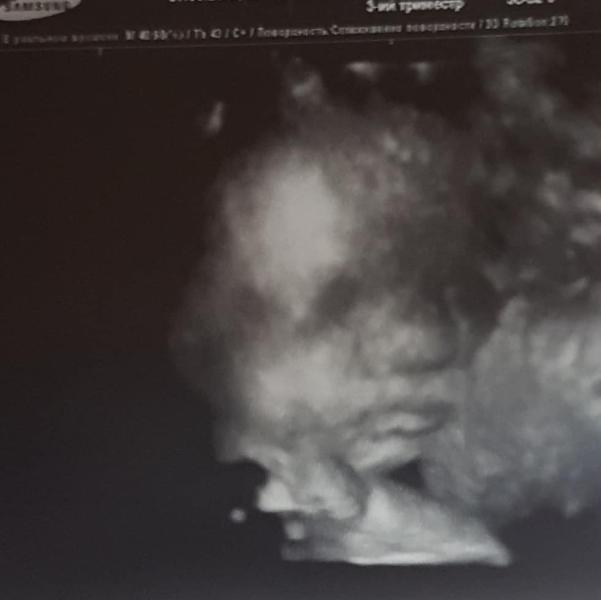

Сегодня была на УЗИ, которое не вписывалось в мои планы, просто так захотела моя сестра. Ради фото 3D. И Я осталась очень довольна! Фото даже немного размытые, на экране все как то по другому что ли... эти красивые губки и носик(такой "маленький") всего лишь в пол экрана)

Вот и мы тоже так ходим) просто чтобы убедиться. Что все хорошо)))

У нас нос на простой фотке тоже странным мне показался, родился с нормальным, отекший был, но не так страшный нос как на фото)

@viktoria_v_teme, малыши же в воде, они все опухшие слегка на 3д фотках))